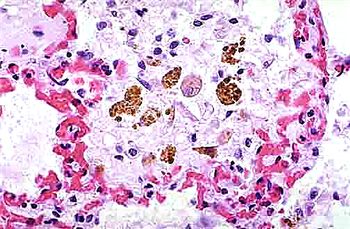

小鼠肺泡巨噬細胞的應用

巨噬細胞,作為免疫系統中的重要成員,以其獨特的吞噬能力和廣泛的生物學功能,在機體的免疫防御、組織修復、炎癥反應調控等方面發揮著至關重要的作用。

吞噬作用 巨噬細胞最顯著的功能是其強大的吞噬能力。它們能夠伸出偽足包圍并吞噬細菌、衰老細胞、凋亡細胞、細胞碎片及病原體等,形成噬體或吞噬小泡,隨后將其消化分解。這一過程不僅有助于清除體內的有害物質,還能激活其他免疫細胞對病原體作出反應。